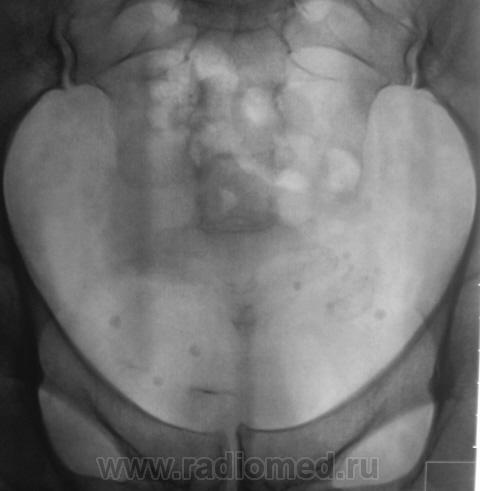

После введения контрастного вещества урограммы произведены на 7 и 15 минутах.

Да, контраст "покрыл" тень рентгеноположительного конкремента.

А мне этот конкремент, при всей его "рентгеноположительности", видится дефектом наполнения чашки, контрастированной ещё более "рентгеноположительным" контрастом)).

Ещё более отчетливо это может было бы увидеть на прицельной рентгенограмме почки либо томограмме её.